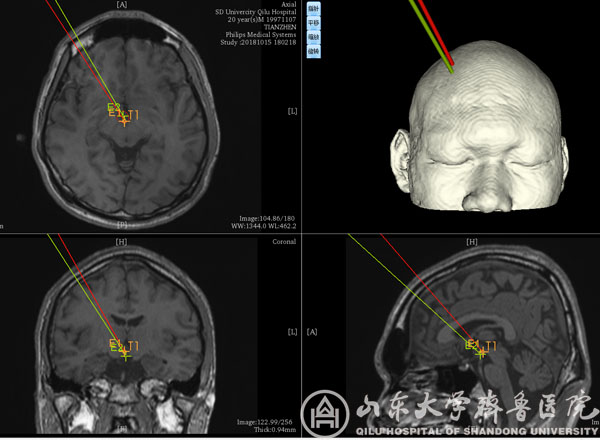

术前计划

该患者男,20岁,发作性头痛、痴笑、左眼向上凝视病史11年,口服丙戊酸钠、拉莫三嗪、鲁米那等多种抗癫痫药物效果欠佳,每日痫性发作仍3~6次,颅脑MRI提示右侧丘脑前下部占位性病变,考虑下丘脑错构瘤。患者收入我院功能神经外科病房后,赵秀鹤副主任带领神经内外科团队共同对患者进行了充分的术前评估,对手术方案进行了深入的讨论,考虑到病变位置重要且深在,开放性开颅手术风险高,术后并发症发生率高,最后决定采用立体定向脑电图引导下射频热凝术的治疗方案。10月21日,徐淑军主任、徐硕主治医师为患者制定了SEEG方案,并在手术机器人引导下成功将颅内电极埋藏在预设手术靶点。经术中CT、多模态影像融合技术以及立体定向脑电监测等多种手段验证靶点后,对致痫灶实施精准射频热凝。术后患者癫痫发作频率较术前减少,未见明显不良反应,已顺利出院,长期疗效正在随访观察中。

作为新兴的癫痫病灶诊断与定位技术,SEEG通过埋藏颅内电极的方式精准捕捉致痫灶起源并明确癫痫传播网络,为难治性癫痫的外科治疗提供依据,必要时还可通过电极热凝对位置较深、范围较小或位于功能区的病变进行毁损,发挥治疗作用。由于对定位精准度要求极高(以毫米计算),传统SEEG电极植入主要依靠立体定向框架系统,但手术操作繁琐,耗时较长,且需要在患者局部麻醉下安装立体定向头架,增加患者心理压力。神经外科手术机器人系统通过无框架定位技术与机械臂辅助,在保证手术精度的同时,简化SEEG手术过程,缩短手术时间,改善患者体验。本次手术是手术机器人系统在我院神经外科首次亮相。除SEEG外,未来机器人还有望应用于颅内病变活检、血肿穿刺引流、术中导航甚至脑深部电刺激器植入等神经外科手术。